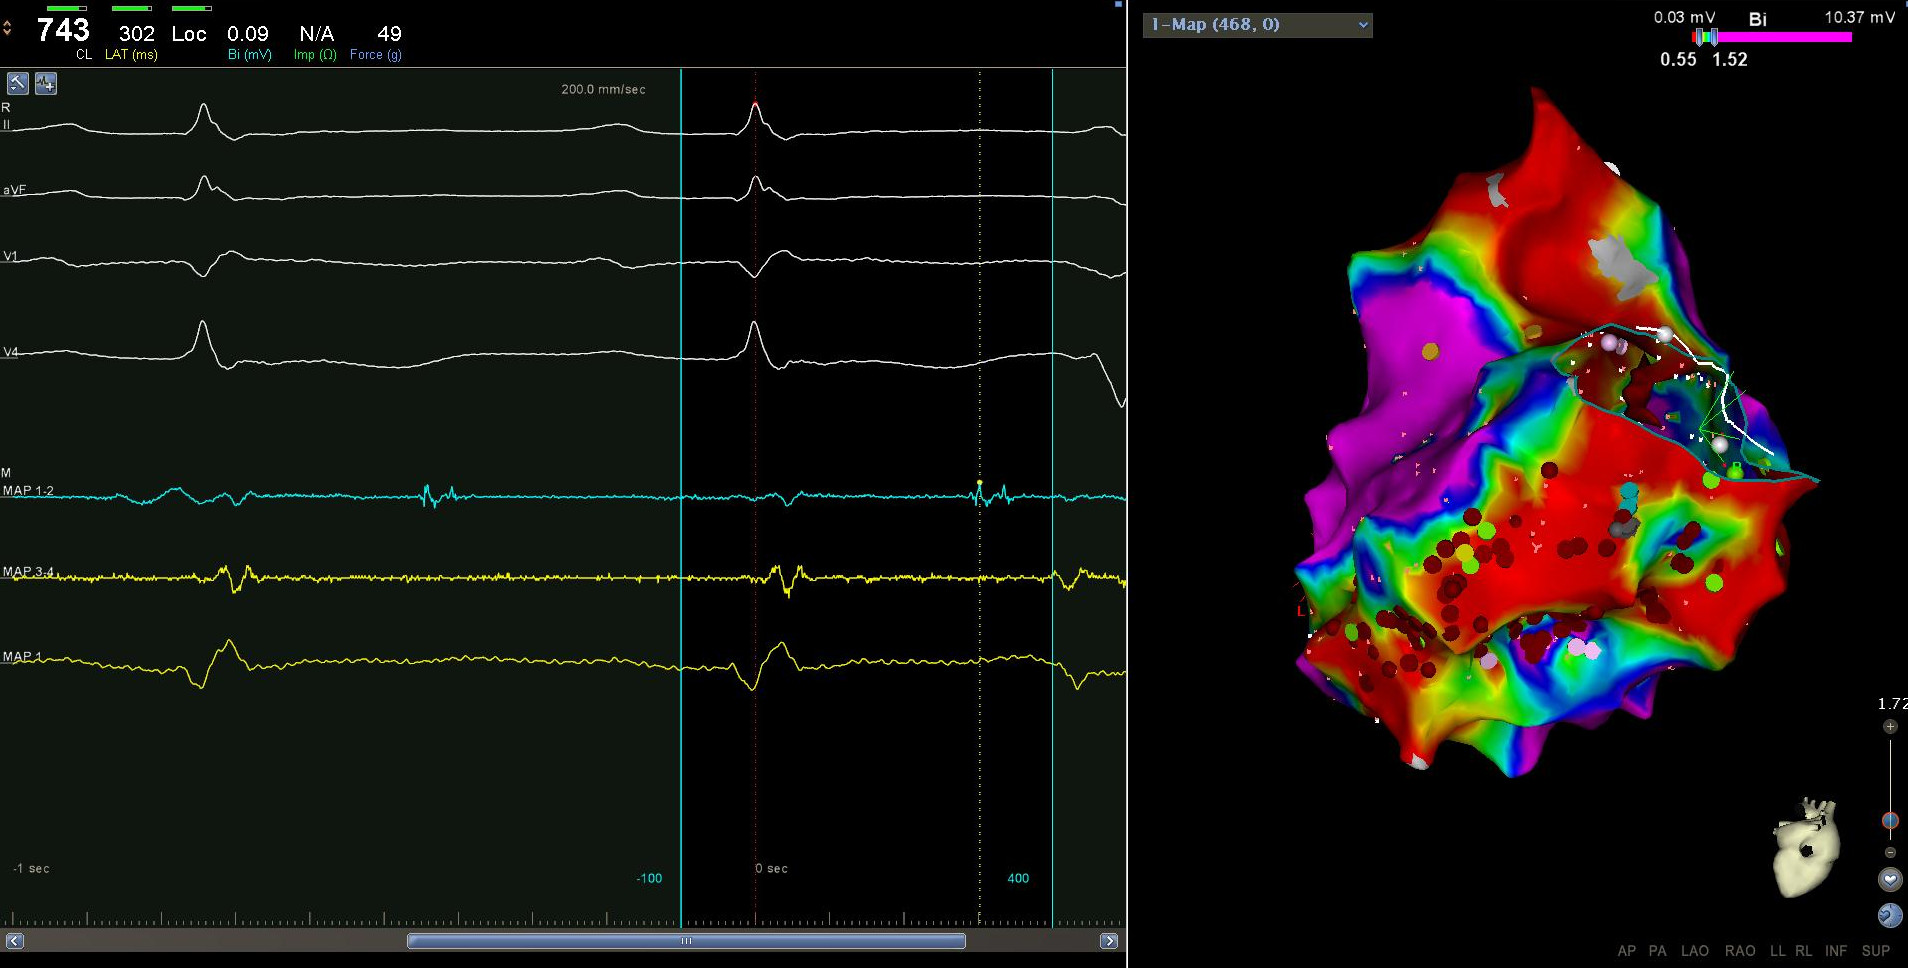

Voltage map

iwmi_isthmus.jpg

voltage map in epicardium

lv_epi_lava.jpg